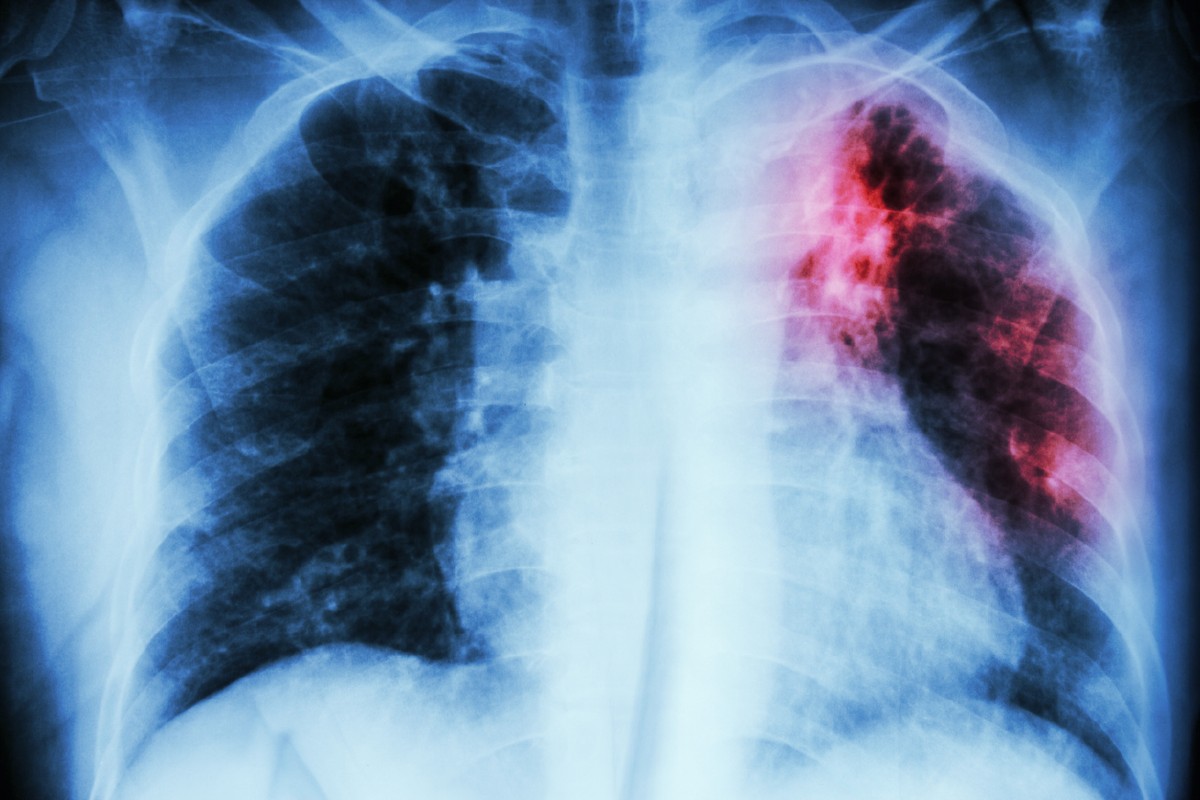

Keuhkotuberkuloosi voi näyttää röntgenkuvassa esimerkiksi tältä. Kuva: iStock